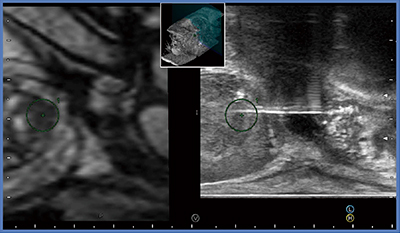

狙撃生検には,最も精度の高いMRIガイド下に直接行う方法や,MRIと経直腸的前立腺超音波検査画像(MR-TRUS)フュージョンガイド下に行うなどの方法があるが,臨床での実用性,簡便性と狙撃効率のバランスに優れたMR-TRUSフュージョンガイド下に行うのが最適と考え,当院でも2012年頃から日立アロカメディカル社の“Real-time Virtual Sonography(RVS)”システムを導入してRVSガイド下狙撃生検を開始し,現在はこれを標準的に行っている。また,狙撃生検の開始と同時期にFocal therapyも開始した。

図1にMR-TRUSフュージョン画像を示す。MRIのボリュームデータをTRUSプローブの磁気センサに同期させて位置合わせを行い,MRIとTRUS画像が同期して動くことを確認してからMRI検出病変にROIをとり,同期したROIをめざして狙撃生検を行っている。

図1 MR-TRUSフュージョン画像